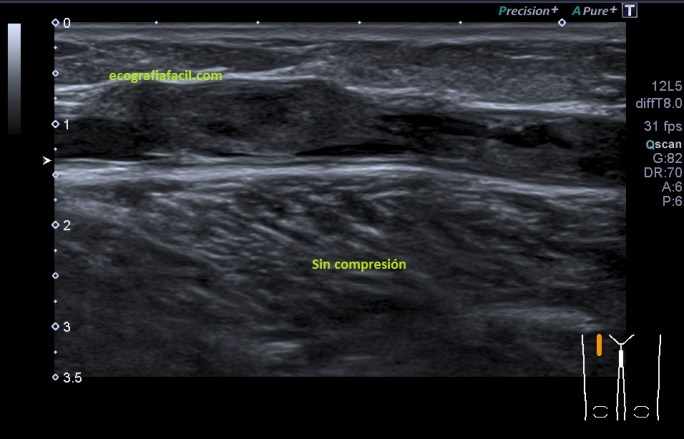

Recorrí de craneal a caudal la estructura y vi que el contenido se mantenía por algunos centímetros, comprimí la estructura, hice el estudio en la misma localización, con y sin compresión, imágenes 5 y 6, supe entonces que era una vena y que el contenido hacía que en algún punto la vena no se comprimiese. Puse doppler color y pulsado,imagen 4, comprobando si el vaso estaba permeable al menos parcialmente y efectivamente, y «escuchando» el sonido del paso de la sangre en ese punto. Ojo siempre a la correcta angulación del Doppler, en este caso no es correcta, solo quería certificar que era una vena, y así era.